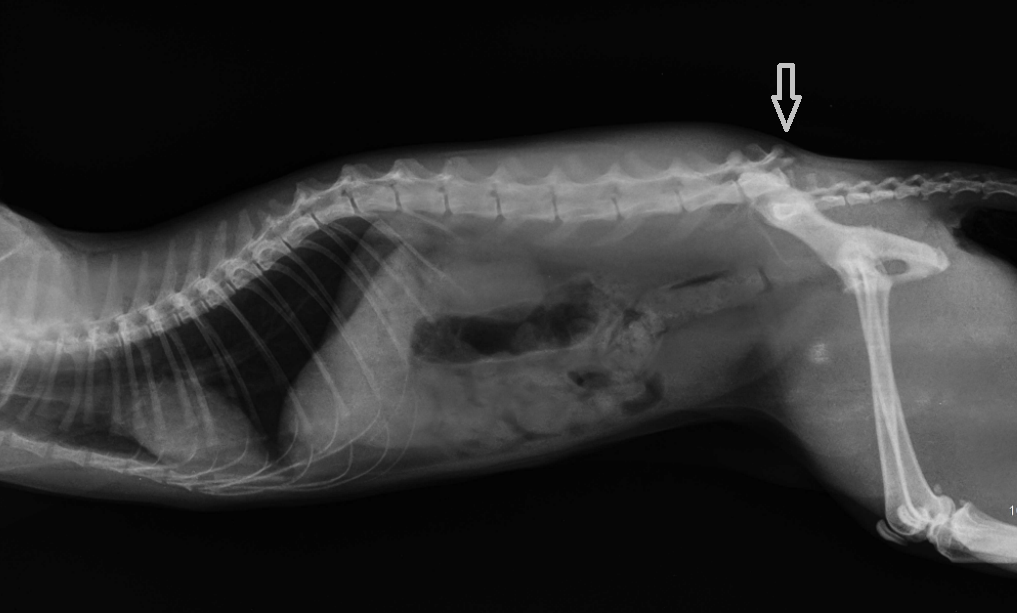

Истончение костей у кошек: причины и решения

Раздел: Мудрость в объективе